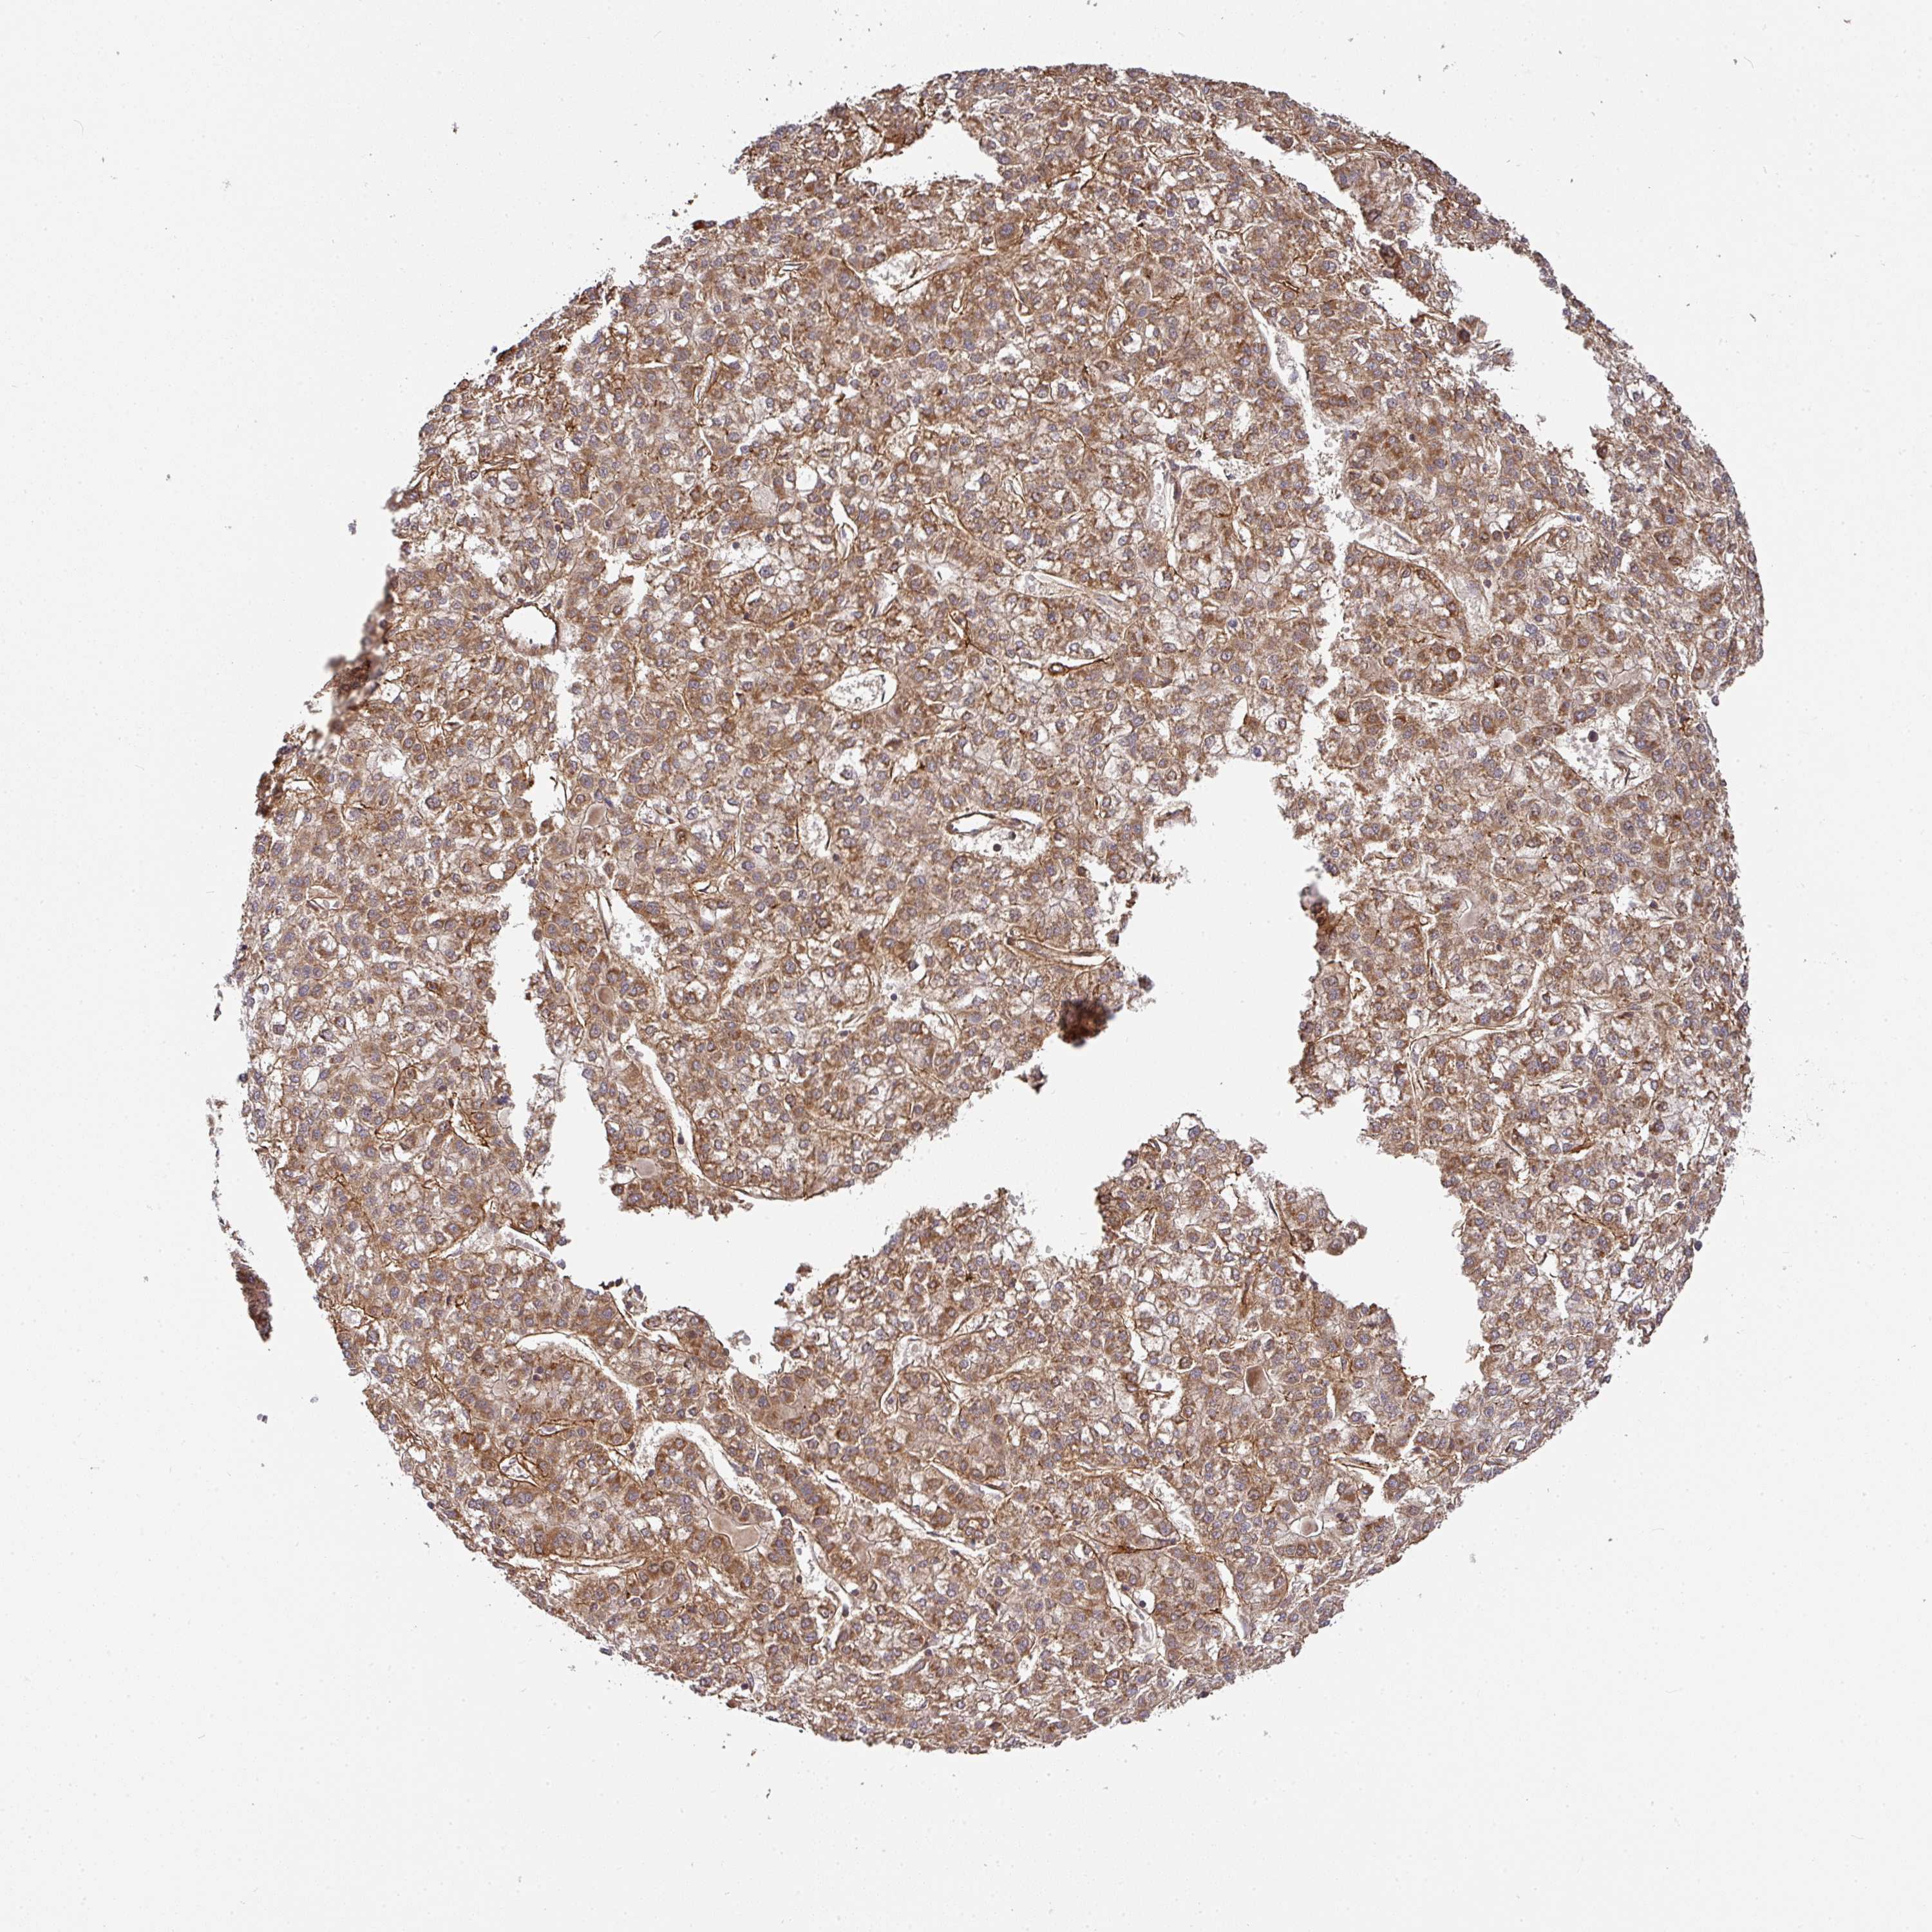

LIVER CANCER - Protein expressioni

A mouse-over function shows sample information and annotation data. Click on an image to view it in a full screen mode. Samples can be filtered based on level of antibody staining by selecting one or several of the following categories: high, medium, low and not detected. The assay and annotation is described here.

Note that samples used for immunohistochemistry by the Human Protein Atlas do not correspond to samples in the TCGA dataset.

Antibody stainingi

Antibody staining in the annotated cell types in the current human tissue is reported as not detected, low, medium, or high, based on conventional immunohistochemistry profiling in selected tissues. This score is based on the combination of the staining intensity and fraction of stained cells.

Each image is clickable and will lead to virtual microscopy that enables deeper exploration of all samples and also displays staining intensity scores, fraction scores and subcellular localization as well as patient and tissue information for each sample.

Antibody HPA051673

Staining

High

Medium

Low

Not detected

Intensity

Strong

Moderate

Weak

Negative

Quantity

>75%

75%-25%

<25%

None

Location

Nuclear

Cytoplasmic/membranous

Cytoplasmic/membranous,nuclear

Carcinoma, Hepatocellular, NOS